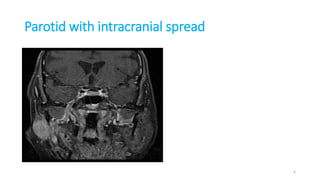

Parotid with intracranial spread